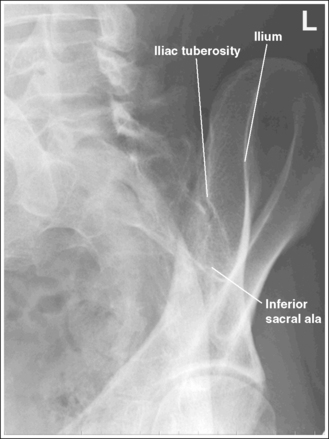

• Determining accuracy of obliquity. The accuracy of an AP oblique sacroiliac joint projection can be determined by the lack of ilium and sacral superimposition. The degree of separation or cavity demonstrated between the ilium and sacrum, which represents the sacroiliac joint, varies from patient to patient. The ilia and sacrum fit very snugly together and in older patients the joint spaces between them may be smaller or even nonexistent because of fibrous adhesions or synostosis. If the patient was not rotated enough to place the ilium and sacral ala in profile, the inferior and superior sacral aspects of the ala are demonstrated without ilium superimposition, whereas the lateral sacral ala is superimposed over the iliac tuberosity (see Image 25). The lateral sacrum is also demonstrated without ilium superimposition. If the patient was rotated more than needed to position the ilium and sacral ala in profile, the ilium is superimposed over the lateral sacral ala and the inferior sacrum (see Image 26).

IMAGE 26

The sacroiliac joint is closed. The superior and inferior sacral alae are demonstrated without iliac superimposition, and the lateral sacral ala is superimposed over the iliac tuberosity. The patient was not rotated enough.

Increase the pelvic obliquity. Because both the sacral ala and the ilium move simultaneously, the adjustment made should be only half the amount of superimposition of the sacral ala and iliac tuberosity.